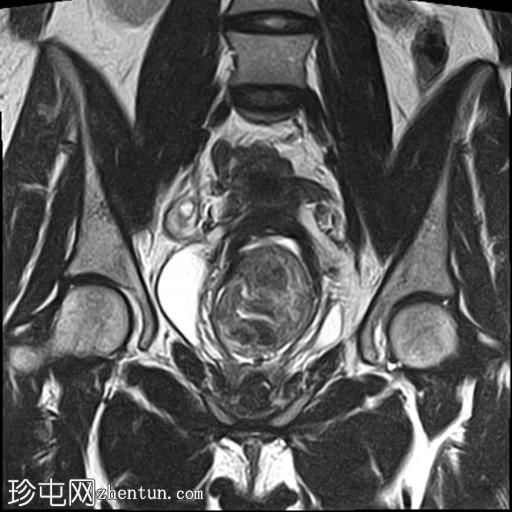

轴位

T2加权像

子宫增大,前倾后屈,可见多发大小不一、位置各异的壁内肌瘤(主要位于Figo 2、5和6区)。

一个边界清晰的带蒂宫腔内肿块经扩张的宫颈管脱出。T1加权像上呈等信号,T2加权像上呈中低信号,周围环绕着高信号的子宫内膜,静脉注射对比剂后呈明显不均匀强化。

双侧卵巢外观正常,可见小卵泡。